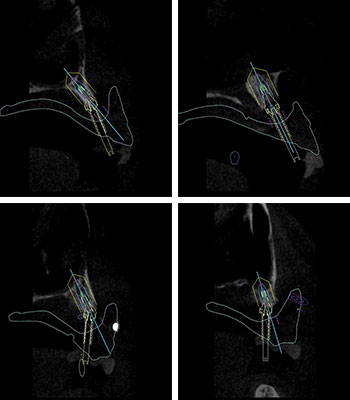

上顎CT (cross-sectional画像)

抜歯後の状態は、全顎に渡り骨量が少ない。特に左上前方は根尖性歯周炎の影響で歯槽骨が大きく失われており、インプラントを入れる事が出来ない。

通常の All-on-4では、前方に2本のインプラントが必要であるが、矢印で示した部位には全く骨量がないので、ここにインプラントを埋入する事は出来ない。

Nobel Clinician Planning3Dシミュレーション

Nobel Clinicianによるインプラント埋入の為の3Dシュミレーション

インプラント埋入手術と同時に術前に用意された固定式の仮歯を入れ、機能性と審美性を短時間で回復する即時荷重を前提としたインプラント治療計画です。

右上後方:通常のインプラントを入れる骨量がない為に、ザイゴマインプラントを使用する事で即時荷重が可能

前方領域から左上後方:左上前方を避け、Nobel Parallel CC を4本入れる事で即時荷重を行う

左上後方:噛み合わせの力等を考慮し、長さ13㎜のインプラントとサイナスリフトを併用したインプラントをⅠ本追加し、右側のザイゴマインプラントを含め合計5本のインプラントで即時荷重を行う

※画像2枚目:左上から時計回りに、右上3相当部位 → 正中相当部位 → 左上5相当部位 → 左上6相当部位